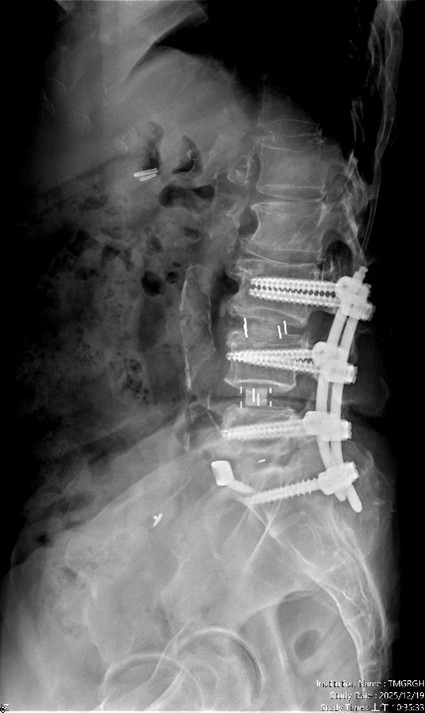

【手術前及手術後】手術前有脊椎滑脫不穩定及脊椎狹窄造成神經壓迫(左圖)。手術後除了重建椎間高度,也將腰椎的生理曲線重建為較理想的前凸狀態(右圖)。【手術前及手術後】手術前有脊椎滑脫不穩定及脊椎狹窄造成神經壓迫(左圖)。手術後除了重建椎間高度,也將腰椎的生理曲線重建為較理想的前凸狀態(右圖)。

【手術前及手術後】手術前有脊椎滑脫不穩定及脊椎狹窄造成神經壓迫(左圖)。手術後除了重建椎間高度,也將腰椎的生理曲線重建為較理想的前凸狀態(右圖)。官方提供